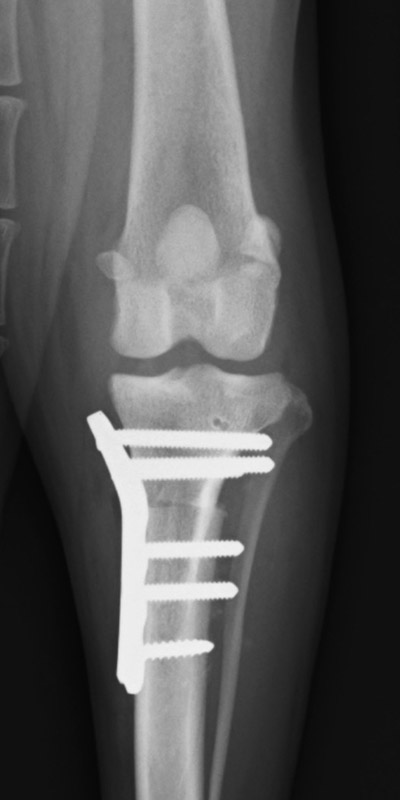

そこで脛骨粗面を切って移動させインプラントで固定することで、膝蓋骨、膝蓋靭帯、および脛骨粗面が真っ直ぐ並ぶようにします。

手術前

手術後